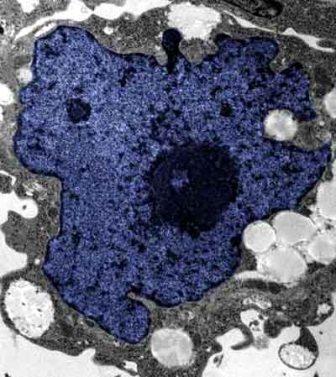

在成人體內(nèi)及胚胎內(nèi)發(fā)現(xiàn)的干細(xì)胞屬于主細(xì)胞,能發(fā)育成各種各樣的組織,可作為人體“修補(bǔ)工具箱”,取代死去及腐壞細(xì)胞組織。此前,最可行的干細(xì)胞為胚胎干細(xì)胞,但它的使用一直受到爭議,因為要在胚胎抽取干細(xì)胞會令胚胎死亡,有人認(rèn)為這樣是變相奪走一條生命。

來自英國和加拿大的兩組研究員所用的新方法不必使用病毒。這項新突破暗示科學(xué)家現(xiàn)在能更認(rèn)真地看待在醫(yī)學(xué)中利用皮膚干細(xì)胞(即誘導(dǎo)多功能干細(xì)胞,俗稱“iPs”細(xì)胞)的前景。

這些細(xì)胞只要配以適當(dāng)?shù)幕瘜W(xué)品和蛋白質(zhì),就能轉(zhuǎn)化成腦神經(jīng)元、制造胰島素的胰腺細(xì)胞、骨或軟骨、心臟肌肉,或其它多種組織。這些細(xì)胞利用病人皮膚來培育,更暗示它們不會被人體排斥。